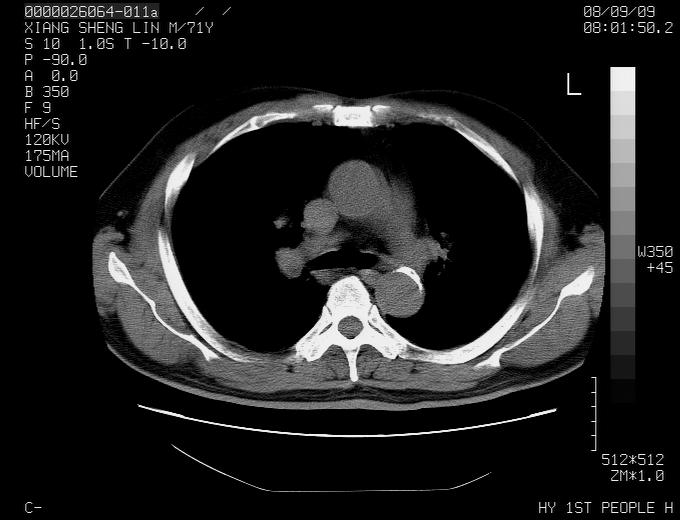

标题: CT15869:男性,71岁,因咳嗽而就诊,请讨论右上肺病变性质 [打印本页]

标题: CT15869:男性,71岁,因咳嗽而就诊,请讨论右上肺病变性质

患者,男性,71岁,因咳嗽而就诊,

肺癌并淋巴结转移。

考虑肺癌并淋巴结转移可能性大

典型的右肺中心性肺癌并纵隔淋巴结转移

右肺中心性肺癌并纵隔淋巴结转移可能性大!

病灶中等程度强化 还是支持肺癌诊断

考虑右肺中心性肺癌并右肺门及纵隔淋巴结转移。

1,右肺中心型ca,气管隆突旁淋巴结转移。

2,右膈明显抬高,建议肝脏扫描排除转移或原发灶。

支持右肺中心性肺癌并右肺门及纵隔淋巴结转移。